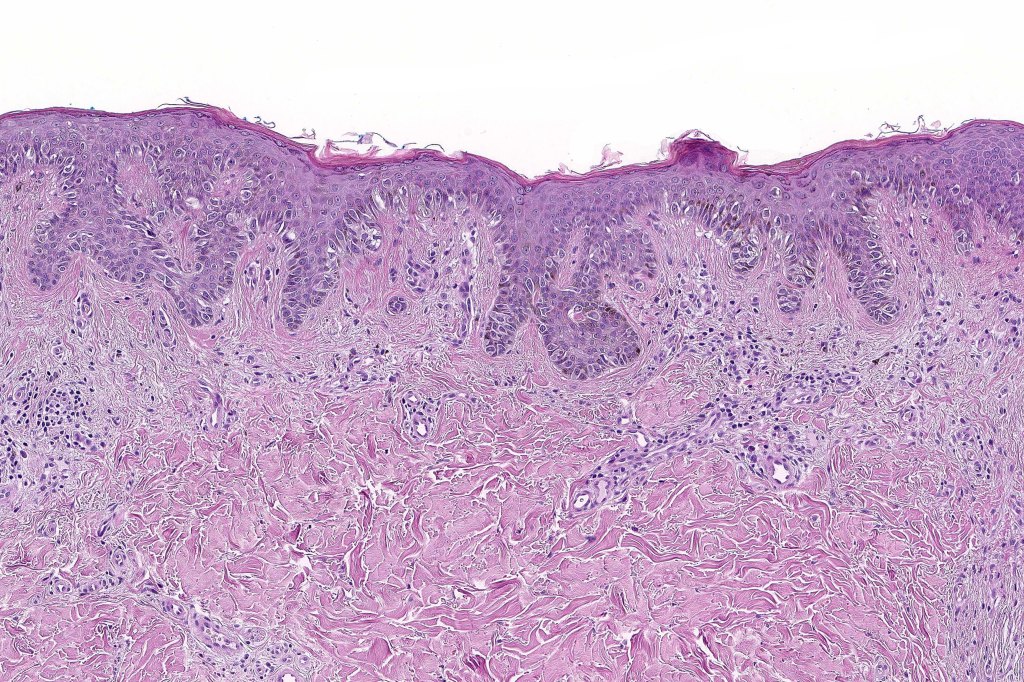

•Architectural disorder- lentiginous and nested, nests abnormally located (at the sides of the rete ridges & overlying the dermal papillae in addition to the tips of the rete ridges rather than solely occupying the tips of the rete ridges as is seen in banal nevi), horizontal orientation & bridging between junctional nests (this should not be confused with bridging between adjacent rete ridge squamous epithelium)

Dysplastic nevus in the majority of cases is instantly recognizable, often at low power. The most important differential diagnosis is obviously melanoma. In junctional lesions, widespread/uniform high grade atypia, frequent mitoses and Pagetoid spread are indicative of in situ melanoma. In compound lesions, dermal nests larger than junctional ones, expansile dermal nests, severe atypia and mitotic activity indicate the presence of melanoma

Dysplastic nevus is sometimes confused with early/evolving Reed nevi. The presence of an almost pure population of uniform, spindled melanocytes, often heavily pigmented nested lesion forming a flattened lower border make the distinction fairly straightforward. Reed nevus is symmetrical & circumscribed.